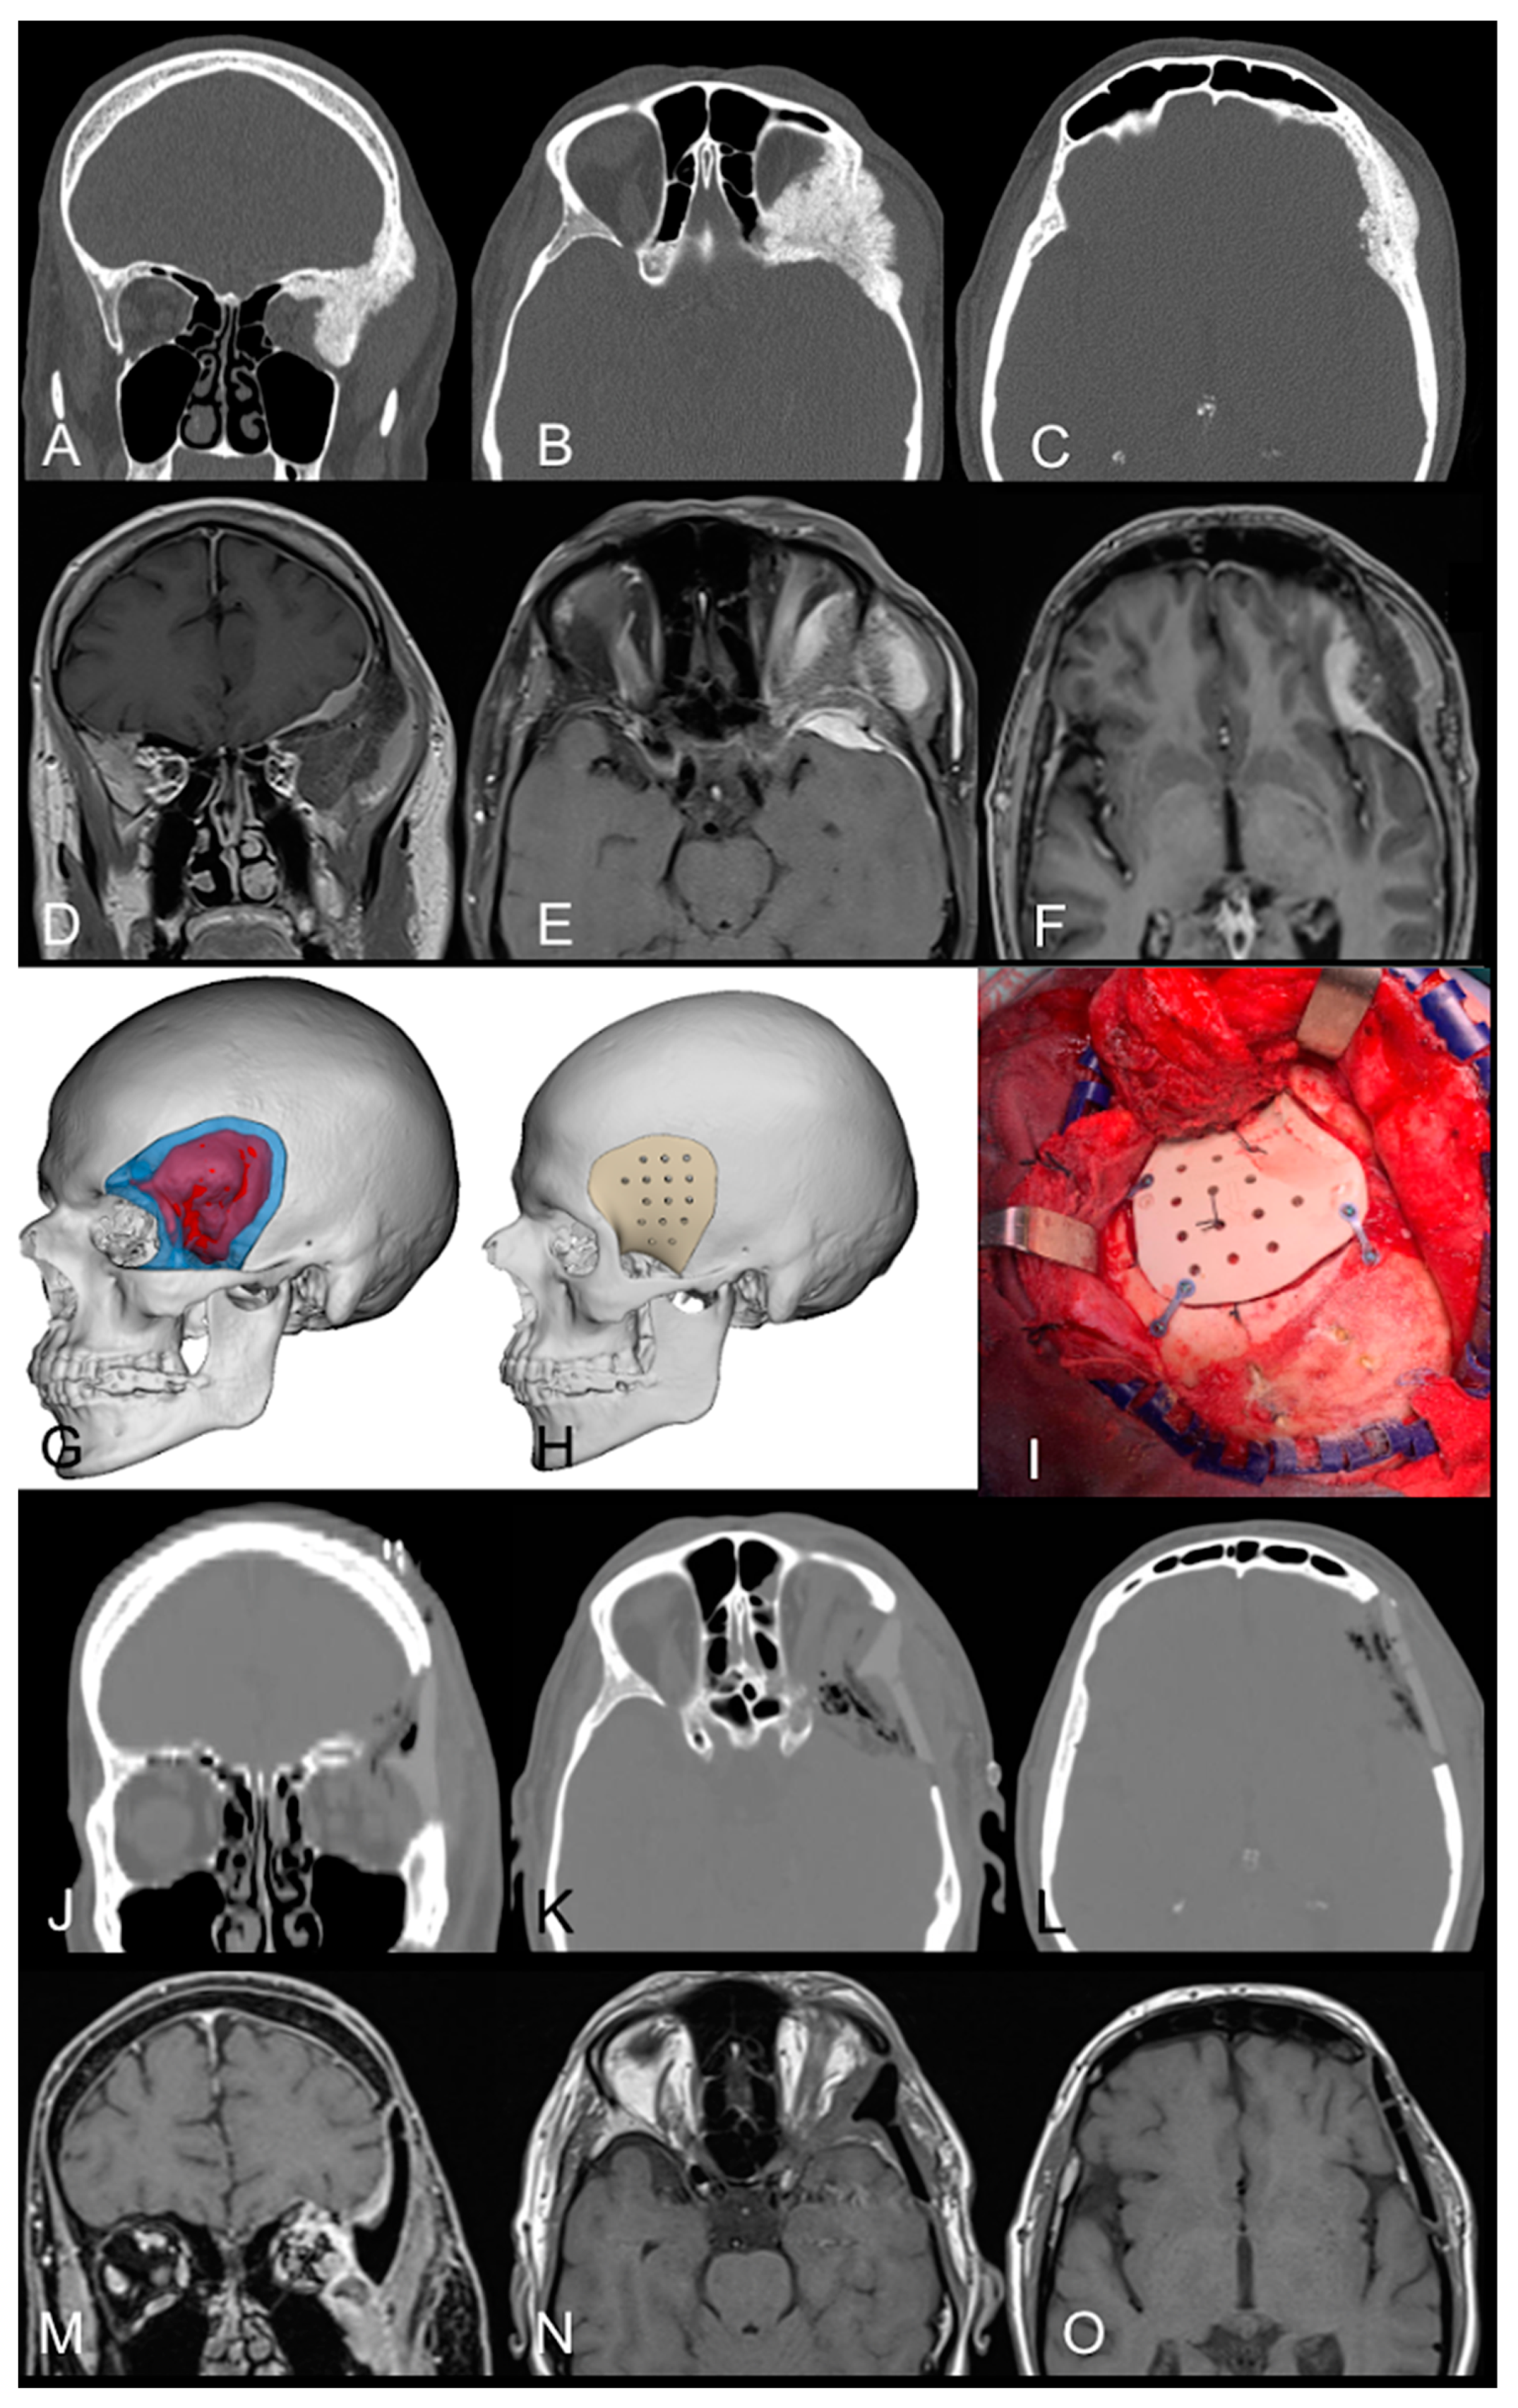

3.2.1. Case Example 1

3.2.2. Case Example 2

| 1 | 60 | M | PEEK | FT | 1 | Ex, D, Ptosis | NT | tVII bleph | N | 0 [9] | 1 | N |

| 2 | 58 | F | PEEK | FT | 1 | Ex, Vis. I Conj Hyp | ST | Intact | N | 0 [19] | 1 | N |